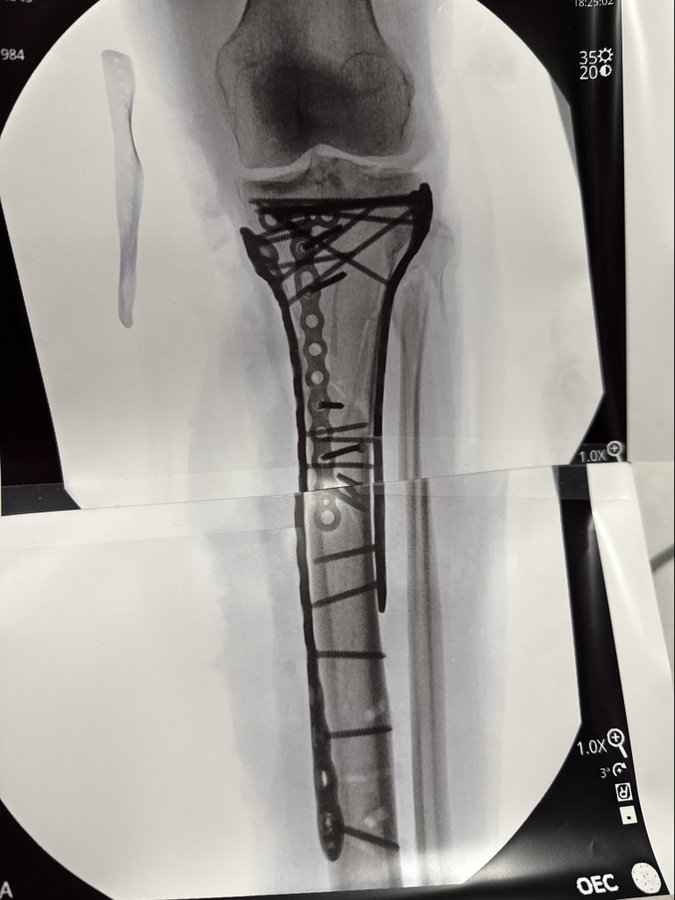

On Friday, Vonn gave fans a glimpse into the aftermath of the accident, posting updates from her hospital bed. Despite the pain being “hard to manage,” she confirmed that her latest surgery “went well,” offering a glimpse of hope amid the terrifying circumstances. Later, she shared graphic X-rays on X, revealing extensive hardware installed throughout her lower leg to stabilize the tibia fracture she sustained in the spill.

“I’m bionic for real now,” Vonn wrote alongside a robotic arm emoji, showcasing her signature humor and resilience even in the face of such adversity. She added that she hopes to “be out of the hospital soon,” expressing gratitude for the flood of support she has received from fans around the world.

The severity of Vonn’s injuries has left experts deeply concerned. Well-known injury analyst Dr. David Chao described the damage as far beyond a typical fracture. “This wasn’t just a fracture; it was a complex open injury with significant knee damage,” he explained, noting that multiple surgeries are expected, including washouts and eventual hardware removal.